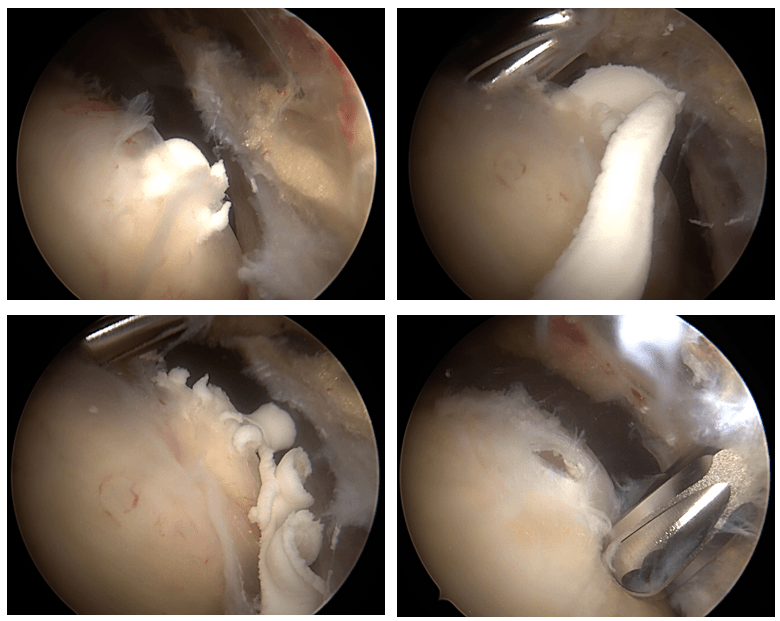

Aspect artroscopic depozit calcaros tendon supraspinos cu evacuare artroscopică